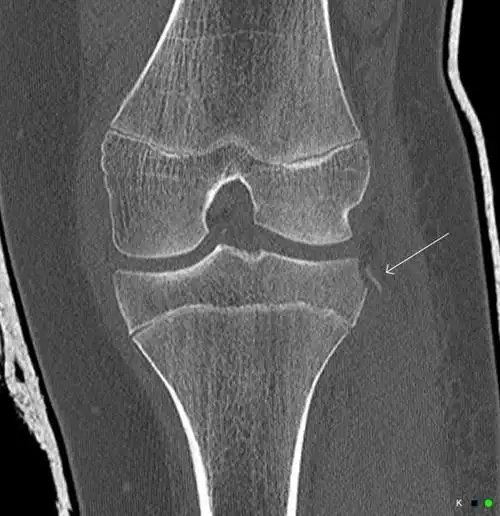

伸直就感觉里边硬邦邦的昨天在家附近医院拍的片子说考虑骨折,让做ct

膝关节后交叉止点撕脱性骨折

术后2月ct